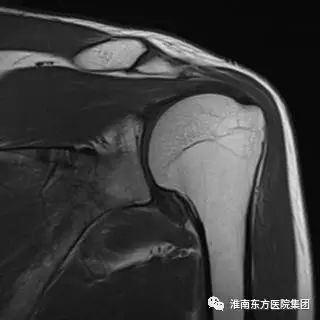

肩关节